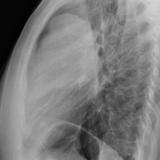

Case 9 Thymoma Lat

Date: 04/04/2010

Views: 3257